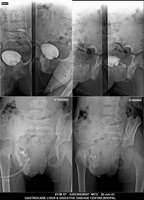

Section: URETHROGRAM

Total: 95 Cases